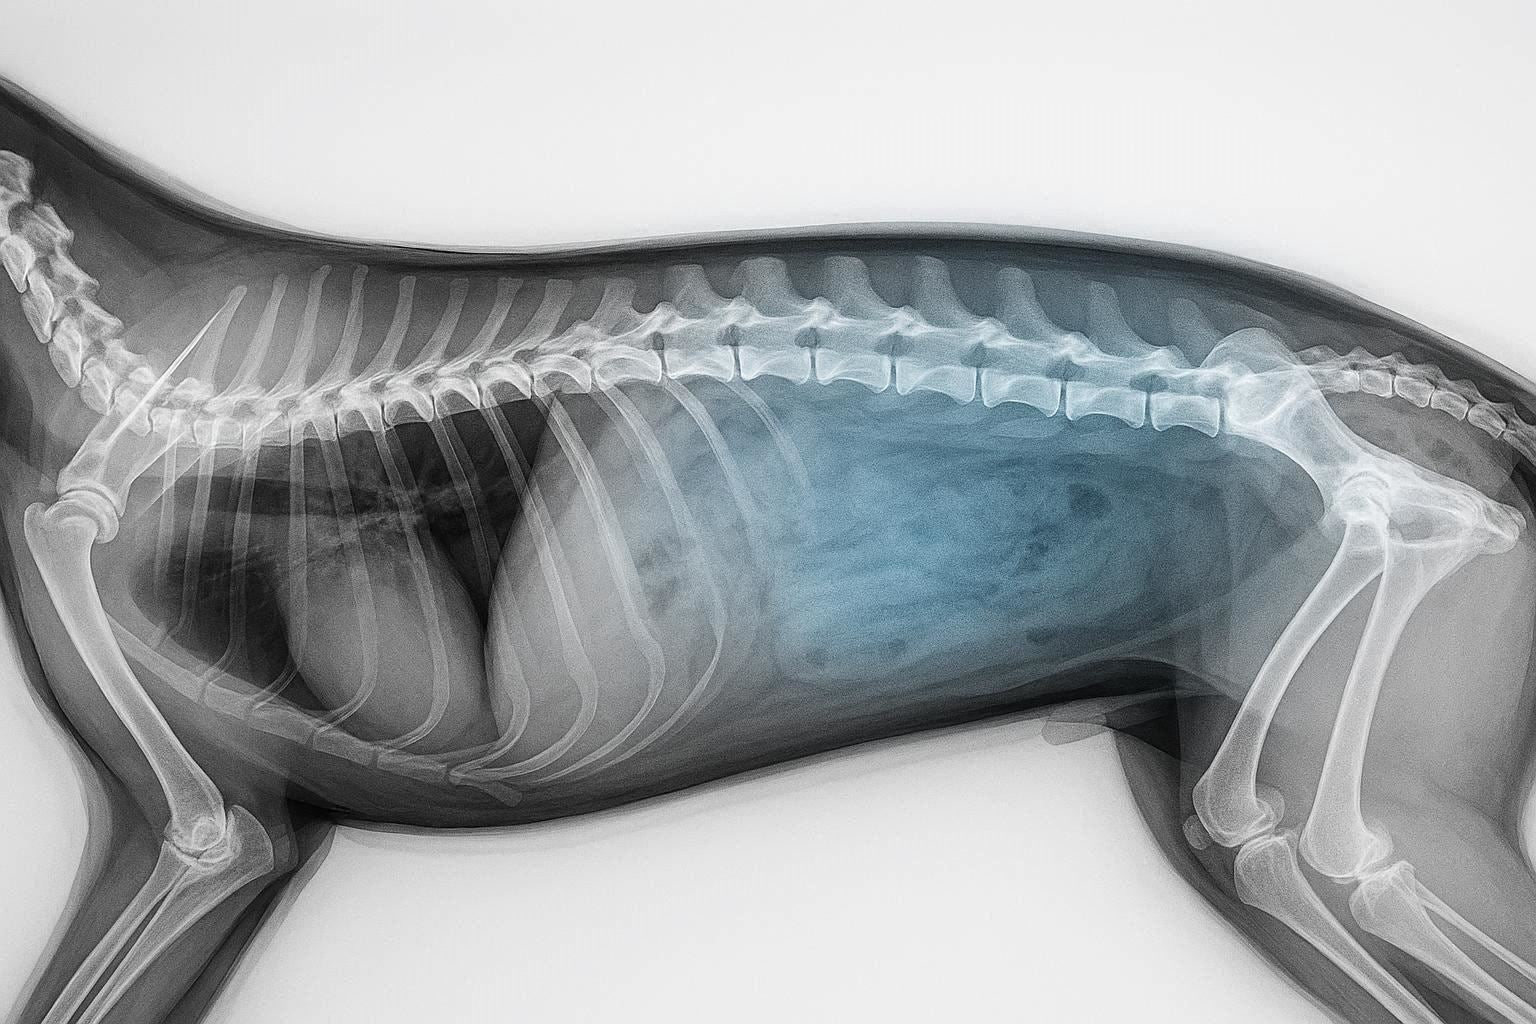

Post-Operative Spinal Care in Dogs: A Comprehensive Veterinary Guide for Optimal Recovery

Spinal surgery in dogs, whether performed to address intervertebral disc disease (IVDD), trauma, congenital abnormalities, or degenerative conditions, marks only...